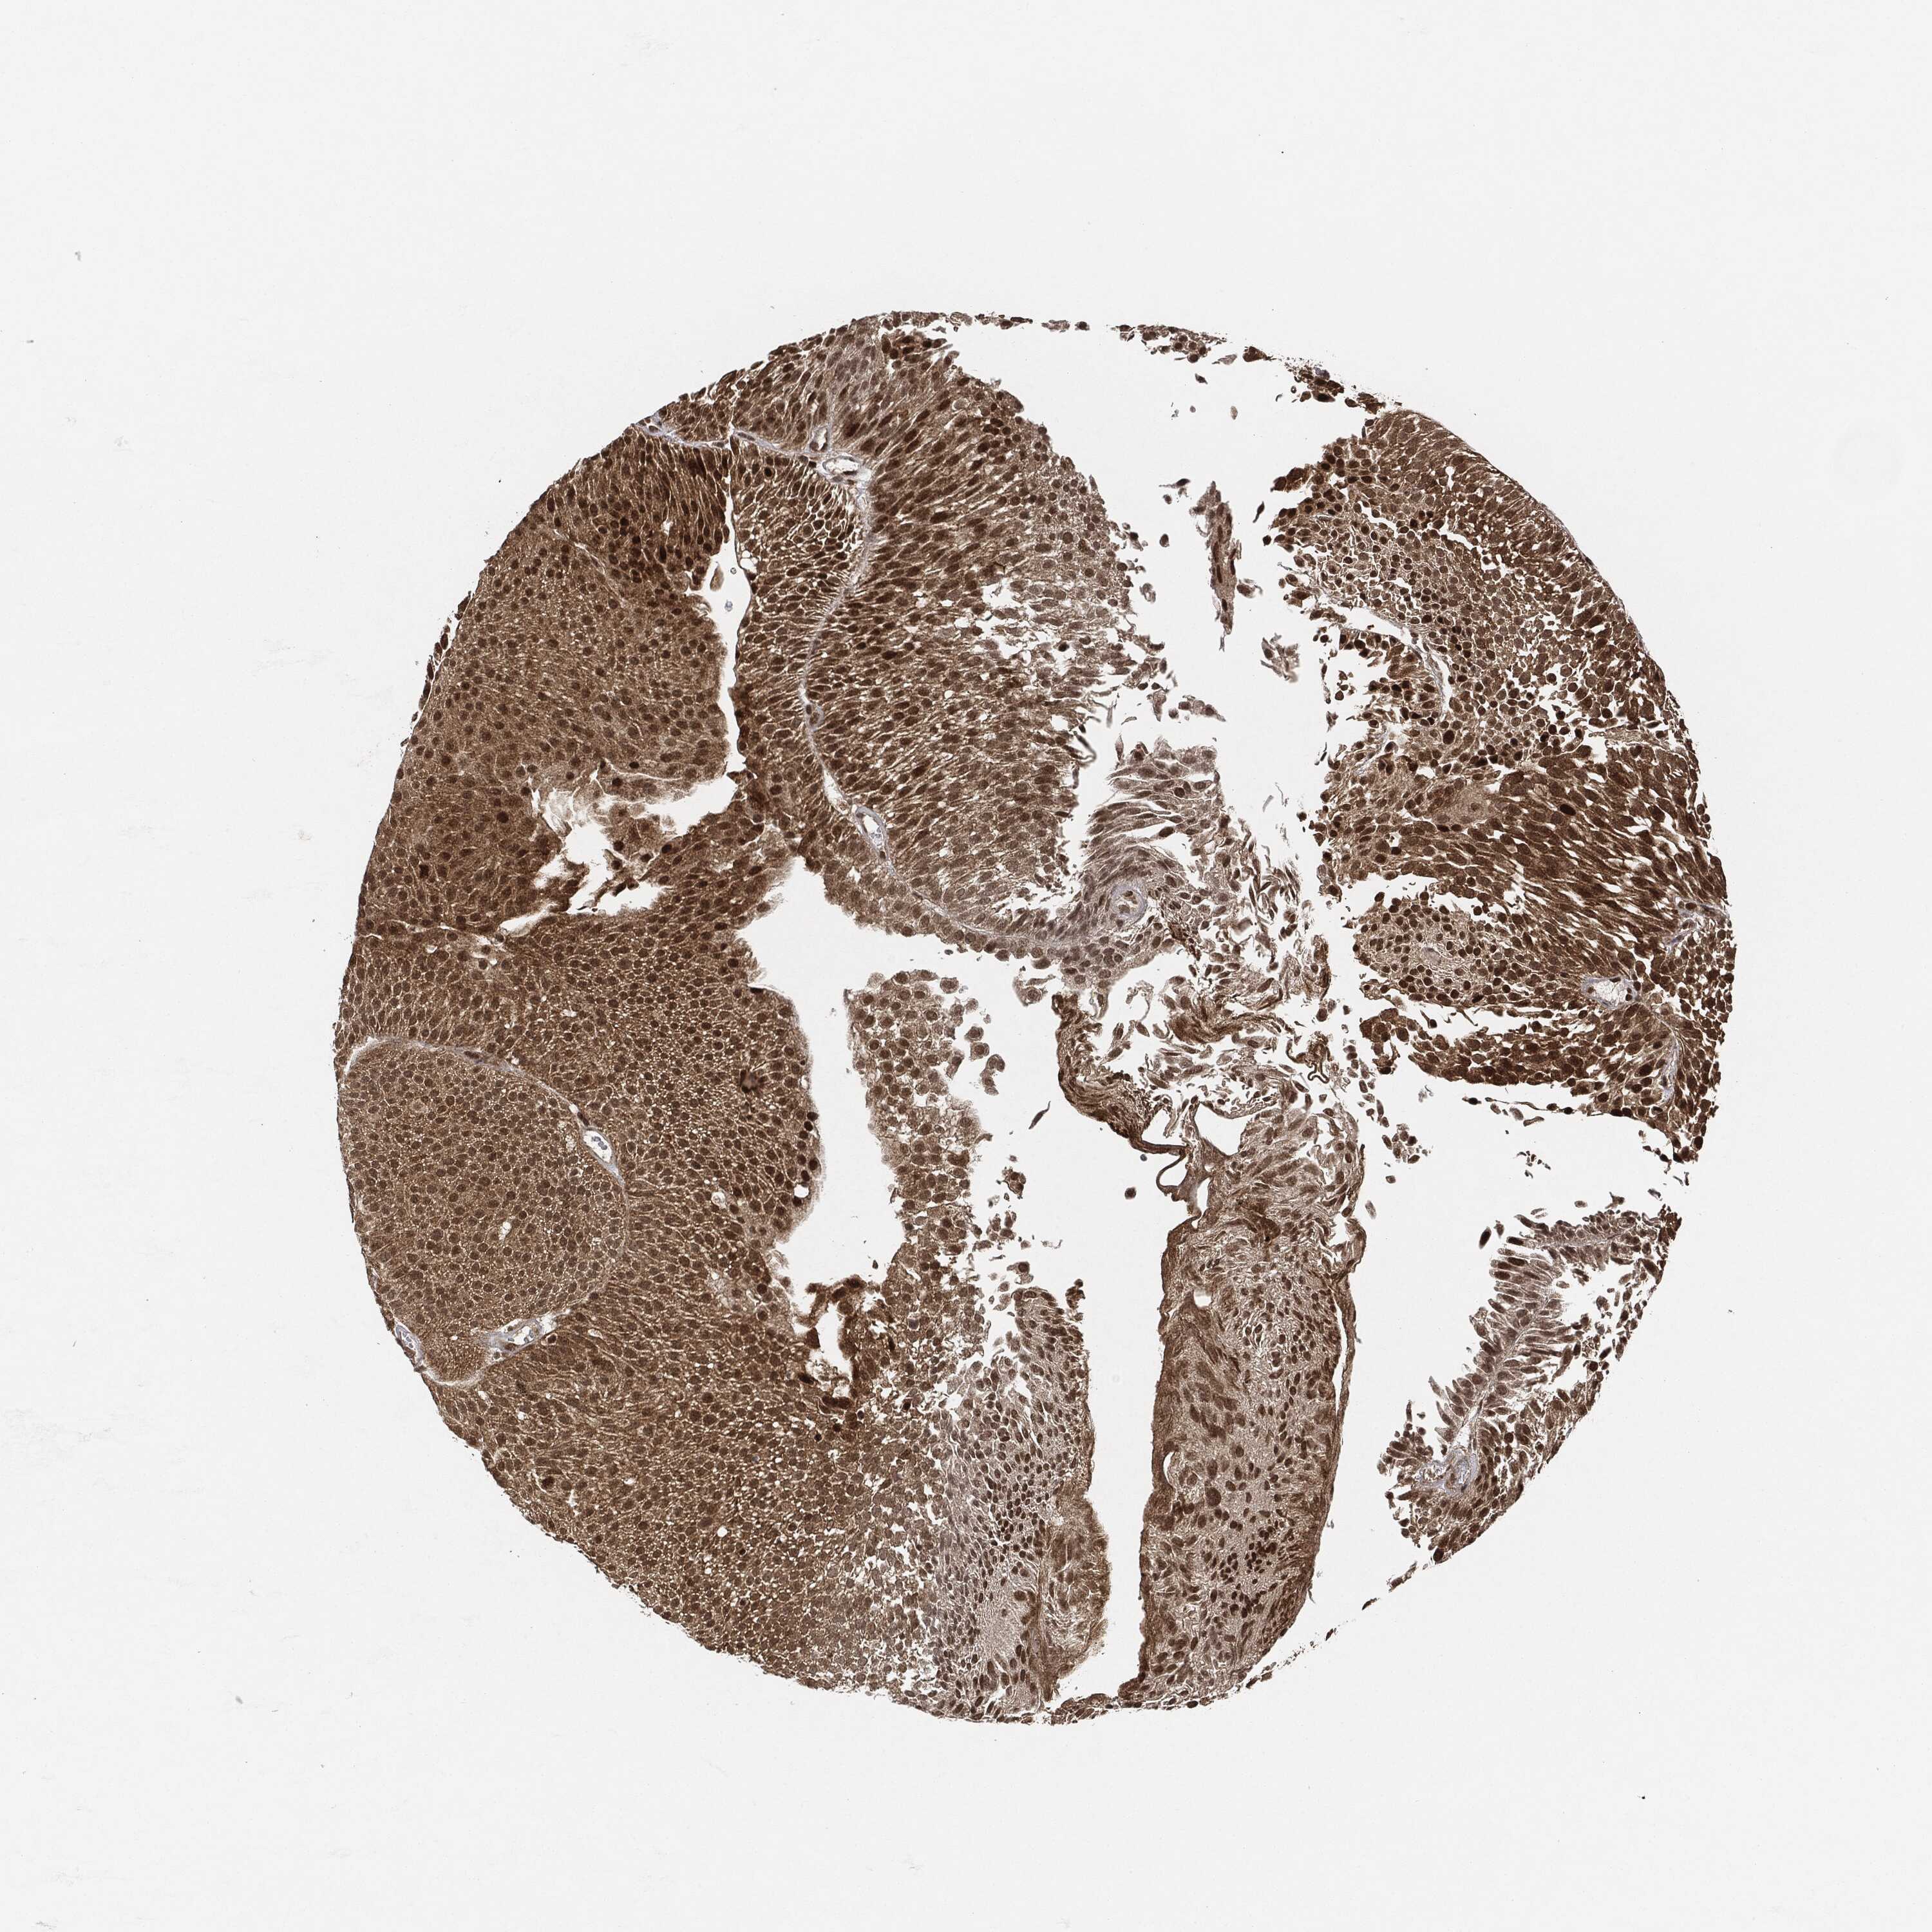

UROTHELIAL CANCER - Protein expressioni

A mouse-over function shows sample information and annotation data. Click on an image to view it in a full screen mode. Samples can be filtered based on level of antibody staining by selecting one or several of the following categories: high, medium, low and not detected. The assay and annotation is described here.

Note that samples used for immunohistochemistry by the Human Protein Atlas do not correspond to samples in the TCGA dataset.

Antibody stainingi

Antibody staining in the annotated cell types in the current human tissue is reported as not detected, low, medium, or high, based on conventional immunohistochemistry profiling in selected tissues. This score is based on the combination of the staining intensity and fraction of stained cells.

Each image is clickable and will lead to virtual microscopy that enables deeper exploration of all samples and also displays staining intensity scores, fraction scores and subcellular localization as well as patient and tissue information for each sample.

HPA001252

Urothelial carcinoma, High grade

Urothelial carcinoma, Low grade

Adenocarcinoma, NOS